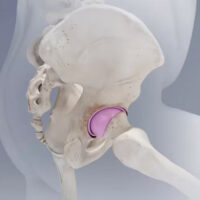

Surgeons at Cleveland Clinic London have begun performing hip resurfacing with ceramic implants. They are among the first in the world to provide this alternative to metal-on-metal hip resurfacing, which currently is recommended only for patients with larger femoral heads.

In response, Prof Cobb and a team of developers produced a novel ceramic hip resurfacing implant, the H1, designed for patients with smaller hips and a smaller pelvis. A 2023 clinical study found that women receiving the H1 had postoperative biomechanics similar to healthy women without hip surgery, while women who had total hip arthroplasty (THA) had worse biomechanics.

Following that publication, Prof Cobb and a team started working toward designing implants, first in metal and later in ceramic, contoured for smaller hips. After four years of preclinical testing to show safety and efficacy, clinical trials of the H1 ceramic implant began in 2017.

By resurfacing the hip instead of replacing it, bone strength is preserved, allowing hip muscles to continue acting normally, he says. Forces are transmitted up the femoral neck and across the hip joint.

With hip resurfacing, patients retain the femoral head and neck, allowing them to resume activities they did with their healthy, native hip. The H1 ceramic hip implant makes hip resurfacing an option for more patients, specifically those with smaller bone structure.